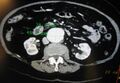

An aortic aneurysm as seen on CT with a small area of remaining blood flow